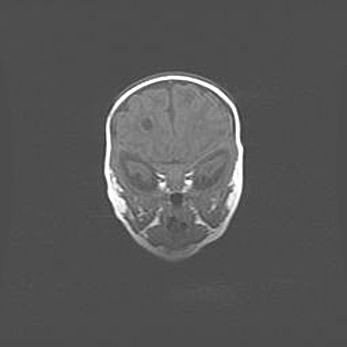

Подострая гематома правой гемисферы мозжечка.

Наружная гидроцефалия.

Возраст: 15 дней

Вес: 3100 г

Пол: женский

Окружность головы: 37 см

Срок гестации: 35-36 недель

При открытой наружной форме гидроцефалии у новорожденных расширяются и переполняются субарахноидные пространства.

Кровоизлияния в мозжечок имеют две клинико-анатомические формы: полушарные гематомы и кровоизлияния в червь.

К появлению этой патологии может привести: повреждения головного мозга, возникающие в результате асфиксии и гипоксии плода при беременности, или травмы во время родов. Редко гематома мозжечка может быть результатом первичной коагулопатии и сосудистой мальформации, диссеминированном внутрисосудистом свертывании, изоиммунной тромбоцитопении.